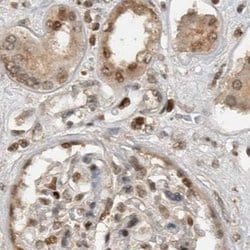

Invitrogen™ ZNF521 Polyclonal Antibody

Brand: Invitrogen™ PA554898

Immunogen sequence: VTVGYTSVSS TTPDSNLSVD SSTMVEAAPP IPKSRGRKRA AQQTPDMTGP SSKQAKVTYS CIYCNKQLFS SLAVLQIHLK TMH Highest antigen sequence identity to the following orthologs: Mouse - 99%, Rat - 99%.

The zinc finger protein 521 (ZNF521) is a transcription factor containing an N-terminal transcriptional repressor motif and 30 zinc finger domains. It plays a role in both erythroid cell and osteoblast differentiation during development, inhibiting the activities of early B-cell factor 1 (EBF1) in erythroid cells and Runx2 in osteoblast precursors. ZFP521 binds to both Runx2 and histone deacetylase 3 (HDAC3), promotes their association and antagonizes Runx2 transcriptional activity in a HDAC3-dependent manner, thereby regulating osteoblast differentiation, skeletal development, and bone homeostasis.

| Immunohistochemistry (Paraffin) | |

| Recombinant protein corresponding to Human ZNF521. Recombinant protein control fragment (Product #RP-93654). | |